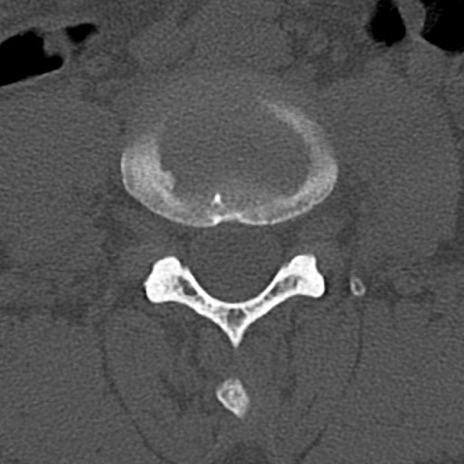

腰椎CT

横断像と矢状断像